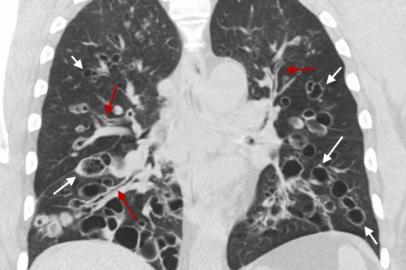

Bronşektazi, akciğerlerde hava taşıyan bronşların iltihaplanması sonucu genişleyerek kronik bir rahatsızlık oluşturuyor.

Sağlık Bakanlığı Koronavirüs Bilim Kurulu Üyesi ve Göğüs Hastalıkları Uzmanı Prof. Dr. Tevfik Özlü, akciğerlere hava taşıyan bronşların iltihap ve enfeksiyon nedeniyle genişlediği kronik bir akciğer rahatsızlığı olan bronşektazi hakkında bilgi verdi. Özlü, "Bronşektazi belirtileri pek çok hastalıkla karıştırılabiliyor. Hastalar uzun yıllar doğru tanı alamıyorlar ve bu da tedaviyi geciktiriyor" dedi.

Bronşektazi hastalarının sıklıkla astım, KOAH veya zatürre gibi farklı hastalıklarla tedavi edildiğini belirten Özlü, "Bu hastalıktaki belirtiler pek çok akciğer hastalığıyla karışabiliyor. Yanlış tanılar ve geciken tedavi, hastaların durumunu daha da kötüleştirebilir. Erken teşhis ve doğru tedavi hayati önem taşıyor" diye konuştu.